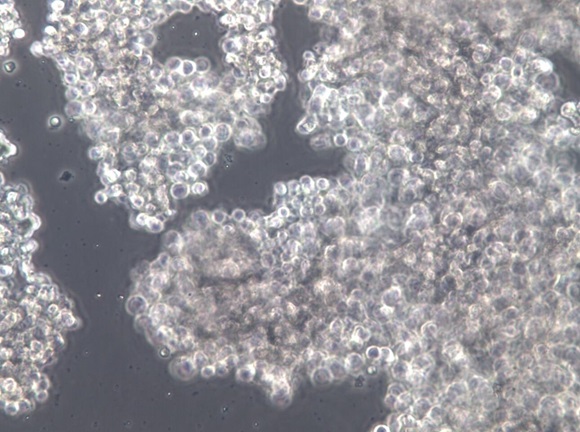

细胞形态 |

成团;淋巴母细胞样 |